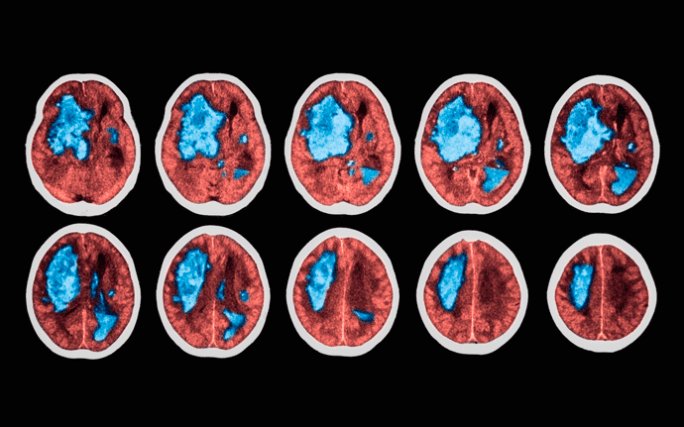

➡️ O AVC atinge 16 milhões de pessoas e no Brasil mata 68 mil pessoas por ano e causa sequelas

➡️ 10 anos atrás, quando eu estava na faculdade, o AVC era mais comum em idosos. Agora isso mudou. O AVC atinge muitas pessoas dos 30 aos 40 anos o que foi comprovado por estudos epidemiológicos

➡️ A atividade física leve ou moderada. protegem da mesma maneira. Elas diminuem em 15% a chance de ter um AVC grave e fatal